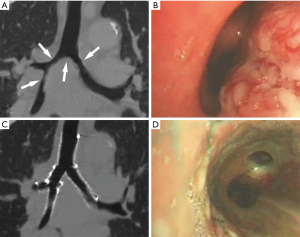

This retrospective study was approved by our institutional review board, and written informed consent was waived. We analyzed the clinical data of patients with malignant airway stenosis involving the carina or bronchi who were treated with implantation of metallic segmented airway stent customized with the aid of 3D printing from January 2017 to May 2019. Patients with tracheoesophageal fistula or patients who underwent both airway and esophageal stenting were excluded. Finally, 12 patients were included in this study. Surgery could not be performed in these patients due to advanced tumor stages. The therapeutic strategy of airway stenting was confirmed by a multidisciplinary discussion attended by thoracic surgeons, pulmonologists, interventional radiologists, and anesthetists. The customized stent was used when the airway stenosis was anatomically complex and difficult to treat with a commercial stent. The use of the stent was approved by the institutional review board and all patients provided written informed consent prior to the procedure. Preoperative chest CT and flexible bronchoscopy were performed to help confirm the location, severity, and range of the stenosis, as well as the anatomical relationship between the airway and the surrounding structures (Figure 1A,B,C,D). The diagnosis of malignant tumors was based on the pathological biopsy results. The 7th American Joint Committee on Cancer/Union for International Cancer Control (AJCC/UICC) staging systems were used to evaluate the tumor stage of these patients.